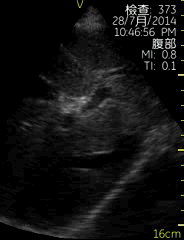

Vscan临床图片 腹部